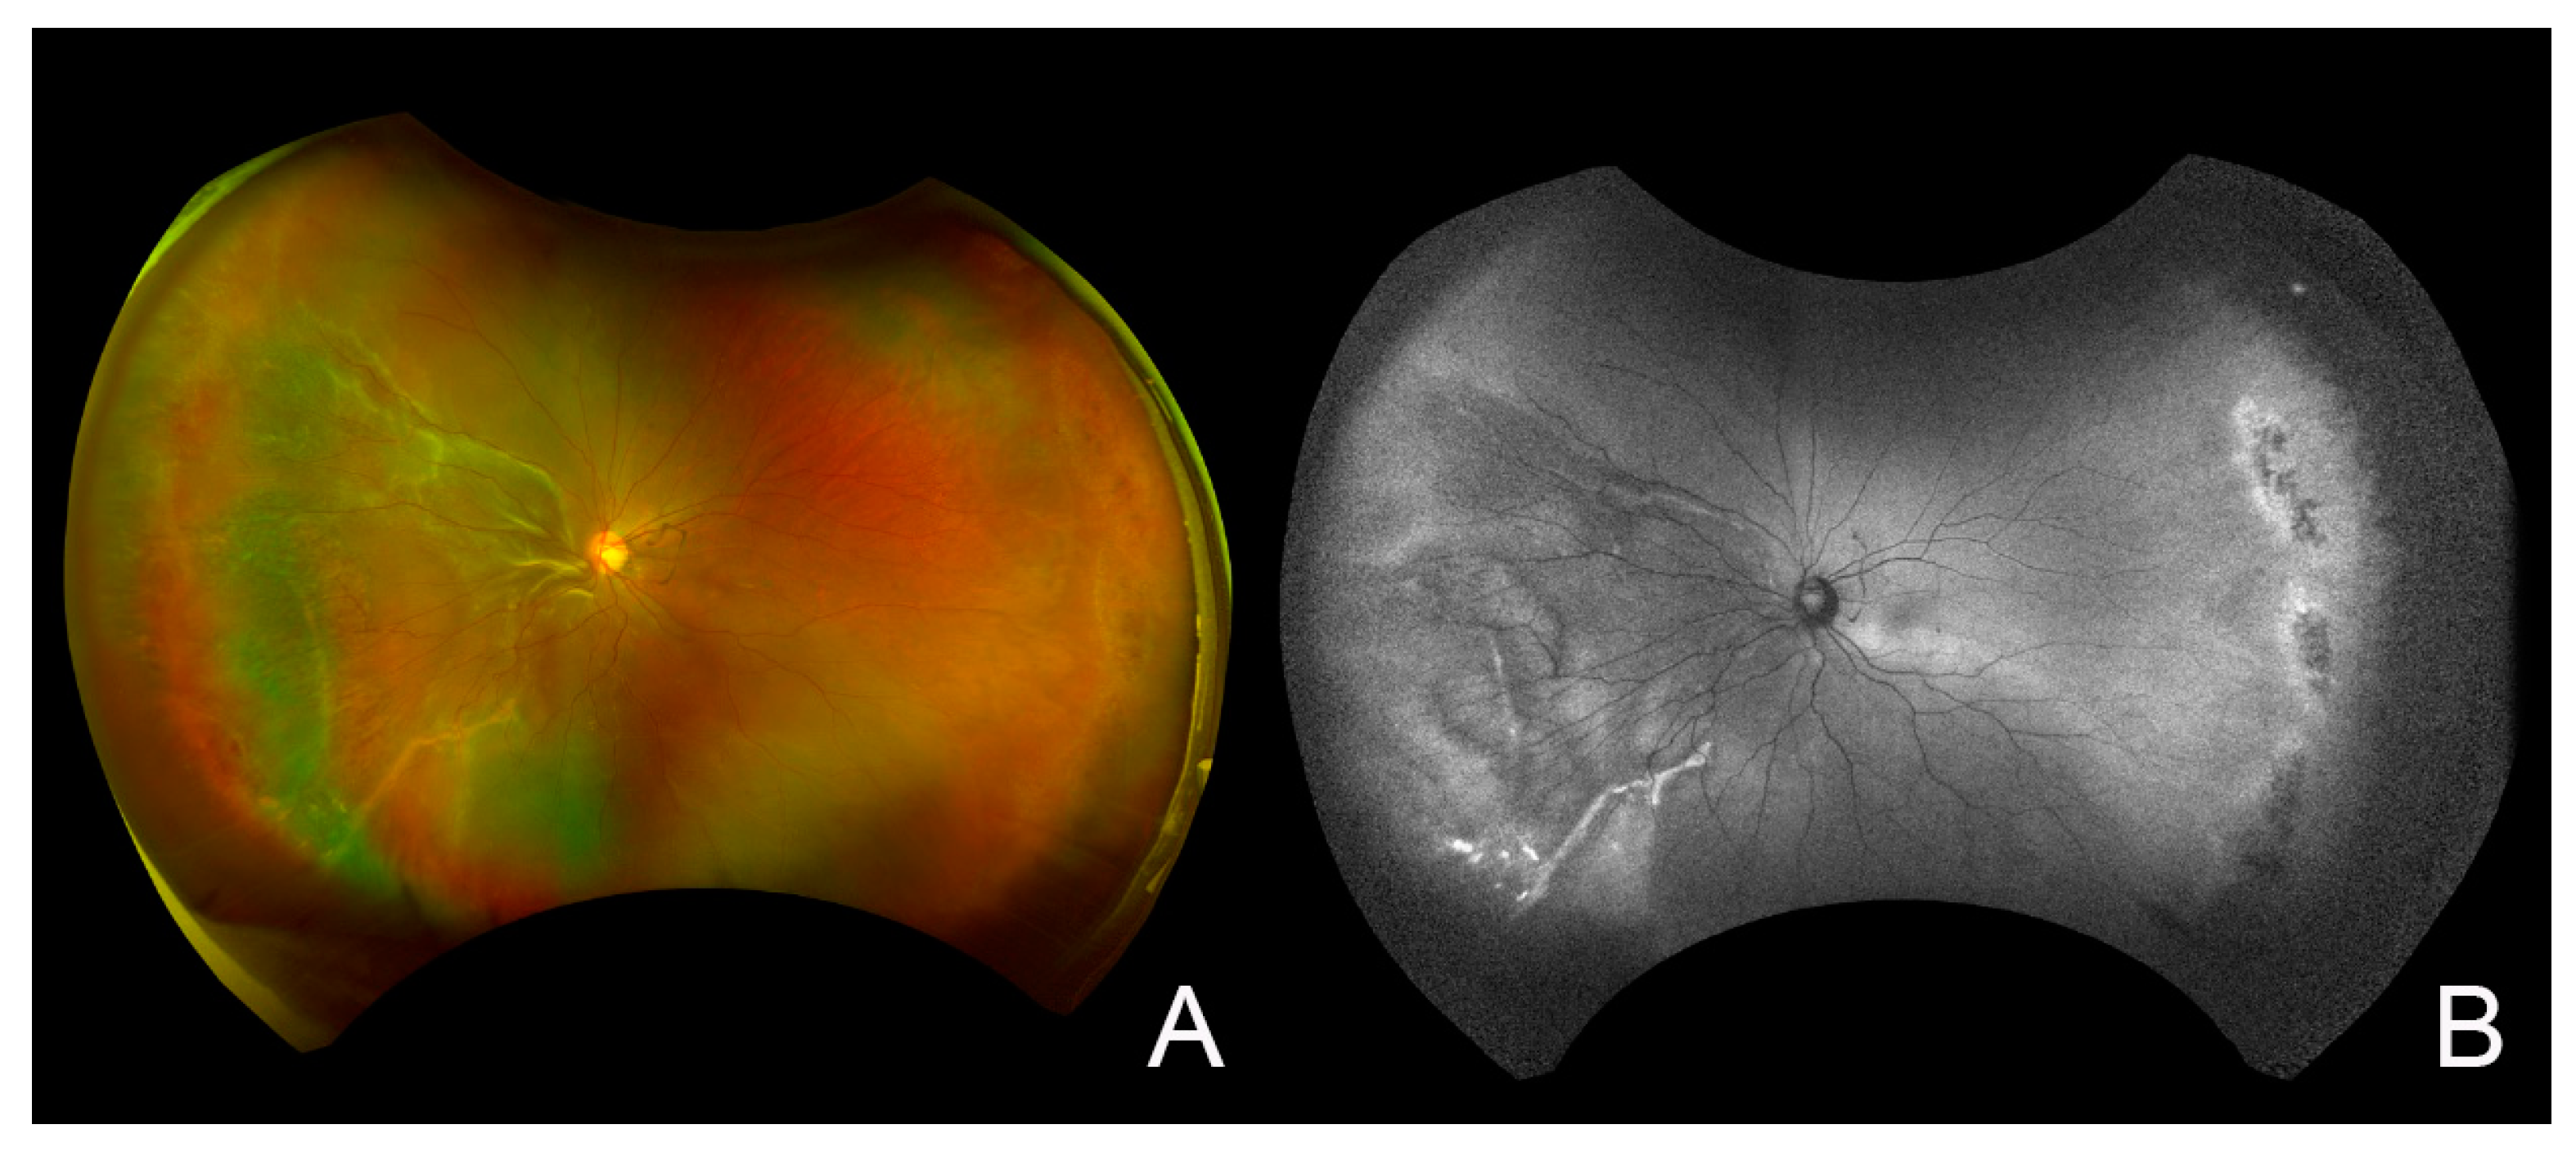

2. Case Report